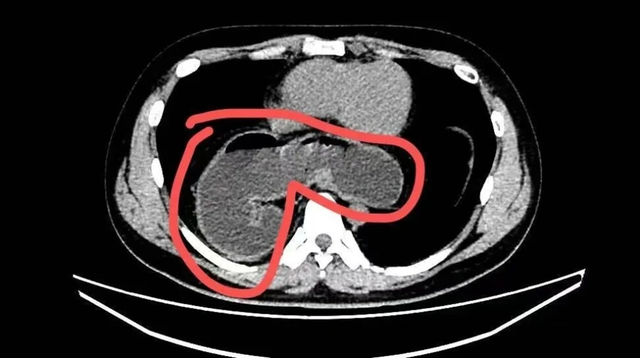

Mãi đến tháng 10 năm ngoái, do ho kéo dài kèm viêm phổi dai dẳng không khỏi, anh được chụp CT phổi. Kết quả khiến cả bệnh nhân lẫn gia đình sững sờ: một phần dạ dày đã “chạy” qua lỗ thực quản lên lồng ngực. Nội soi sau đó xác định anh mắc thoát vị khe thực quản kèm viêm thực quản trào ngược và xoắn dạ dày. Rất may, anh được phẫu thuật xâm lấn tối thiểu và xuất viện chỉ sau 3 ngày.

Theo bác sĩ, thoát vị khe thực quản xảy ra khi lỗ tự nhiên trên cơ hoành - nơi thực quản đi từ ngực xuống bụng - bị giãn rộng bất thường. Khi “cánh cửa” này lỏng ra, dạ dày, thậm chí cả ruột hoặc lách, có thể bị đẩy ngược lên khoang ngực. Hệ quả là axit dạ dày dễ trào ngược gây nóng rát, ợ chua, khó nuốt, đau ngực; nặng hơn có thể dẫn đến xoắn dạ dày, tắc nghẽn, không ăn uống được.